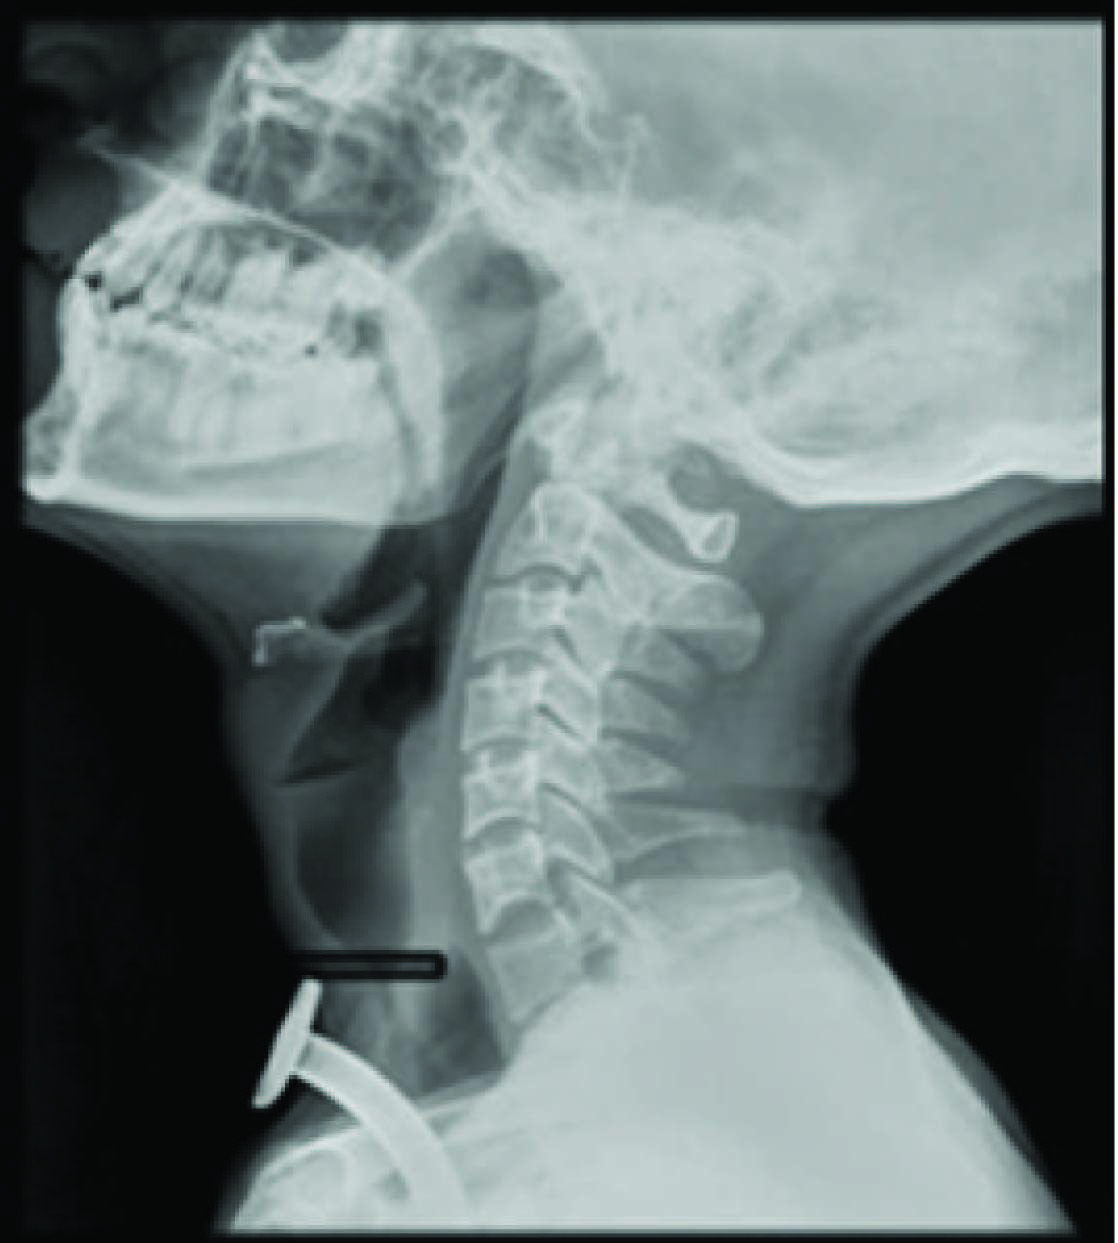

On Examination: Patient was averagely built and well nourished, conscious, comfortable, and could speak clearly by closing tracheostomy tube [Table/Fig-1]. Patient was on nasogastric tube no.14 in-situ. On examination his vital parameters were pulse rate was 78/minute, blood pressure 110/74mmhg and respiratory rate 18/minute. His Spo2 was maintained 100% on room air on auscultation of lungs, bilateral air entry was equal and no added sounds were noted. Other systemic examination findings were within the physiological normal limit. Patient MPC was grade I. Chest X-ray showed the metal tracheostomy tube in-situ with sub-glottic stenosis above tracheostomy tube more evident in lateral view [Table/Fig-2,3].

Level of sub glottis stenosis